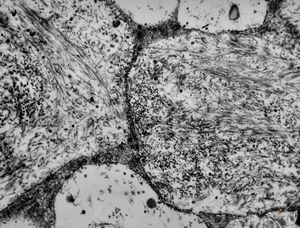

M, 1y. | gangliosidosis - liver